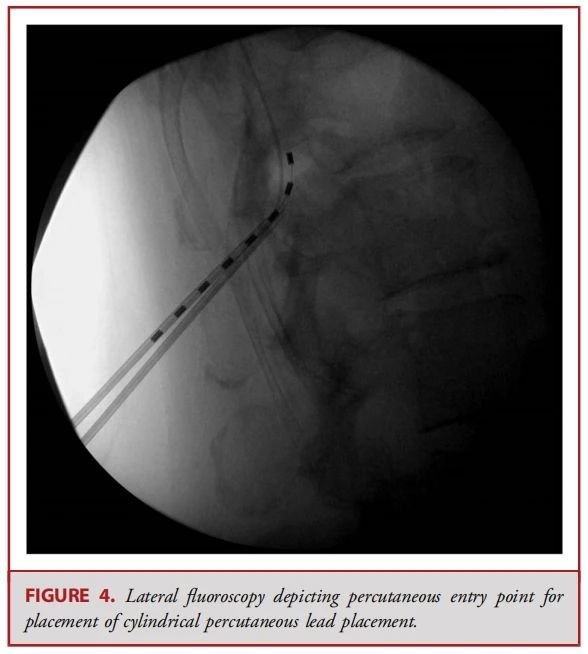

● 经皮电极通常由 8 个球形接触点组成,而鳍状电极则通常具有16至20个接触点,且所有接触点都平铺在硬膜表面(见图 1-3)。经皮电极通常通过改良版的 Tuohy 导管进行插入(见图 4)。在使用失去阻力法进入硬膜外腔后,电极在透视引导下被推进至与疼痛部位相应的脊髓节段(见图 5)。经皮电极和鳍状电极在镇痛效果上具有相似的疗效。经皮电极植入属于较低侵入性的手术,术后并发症的发生率较低(2.2%,相较于鳍状电极3.4%),因此对于合并症较多的患者来说,是一种更为理想的选择。鳍状电极虽然更具侵入性,但与圆柱形经皮电极相比,电极移位的发生频率较低。由于鳍状电极具有更多接触点,因此可以实现更为精准和高效的刺激。